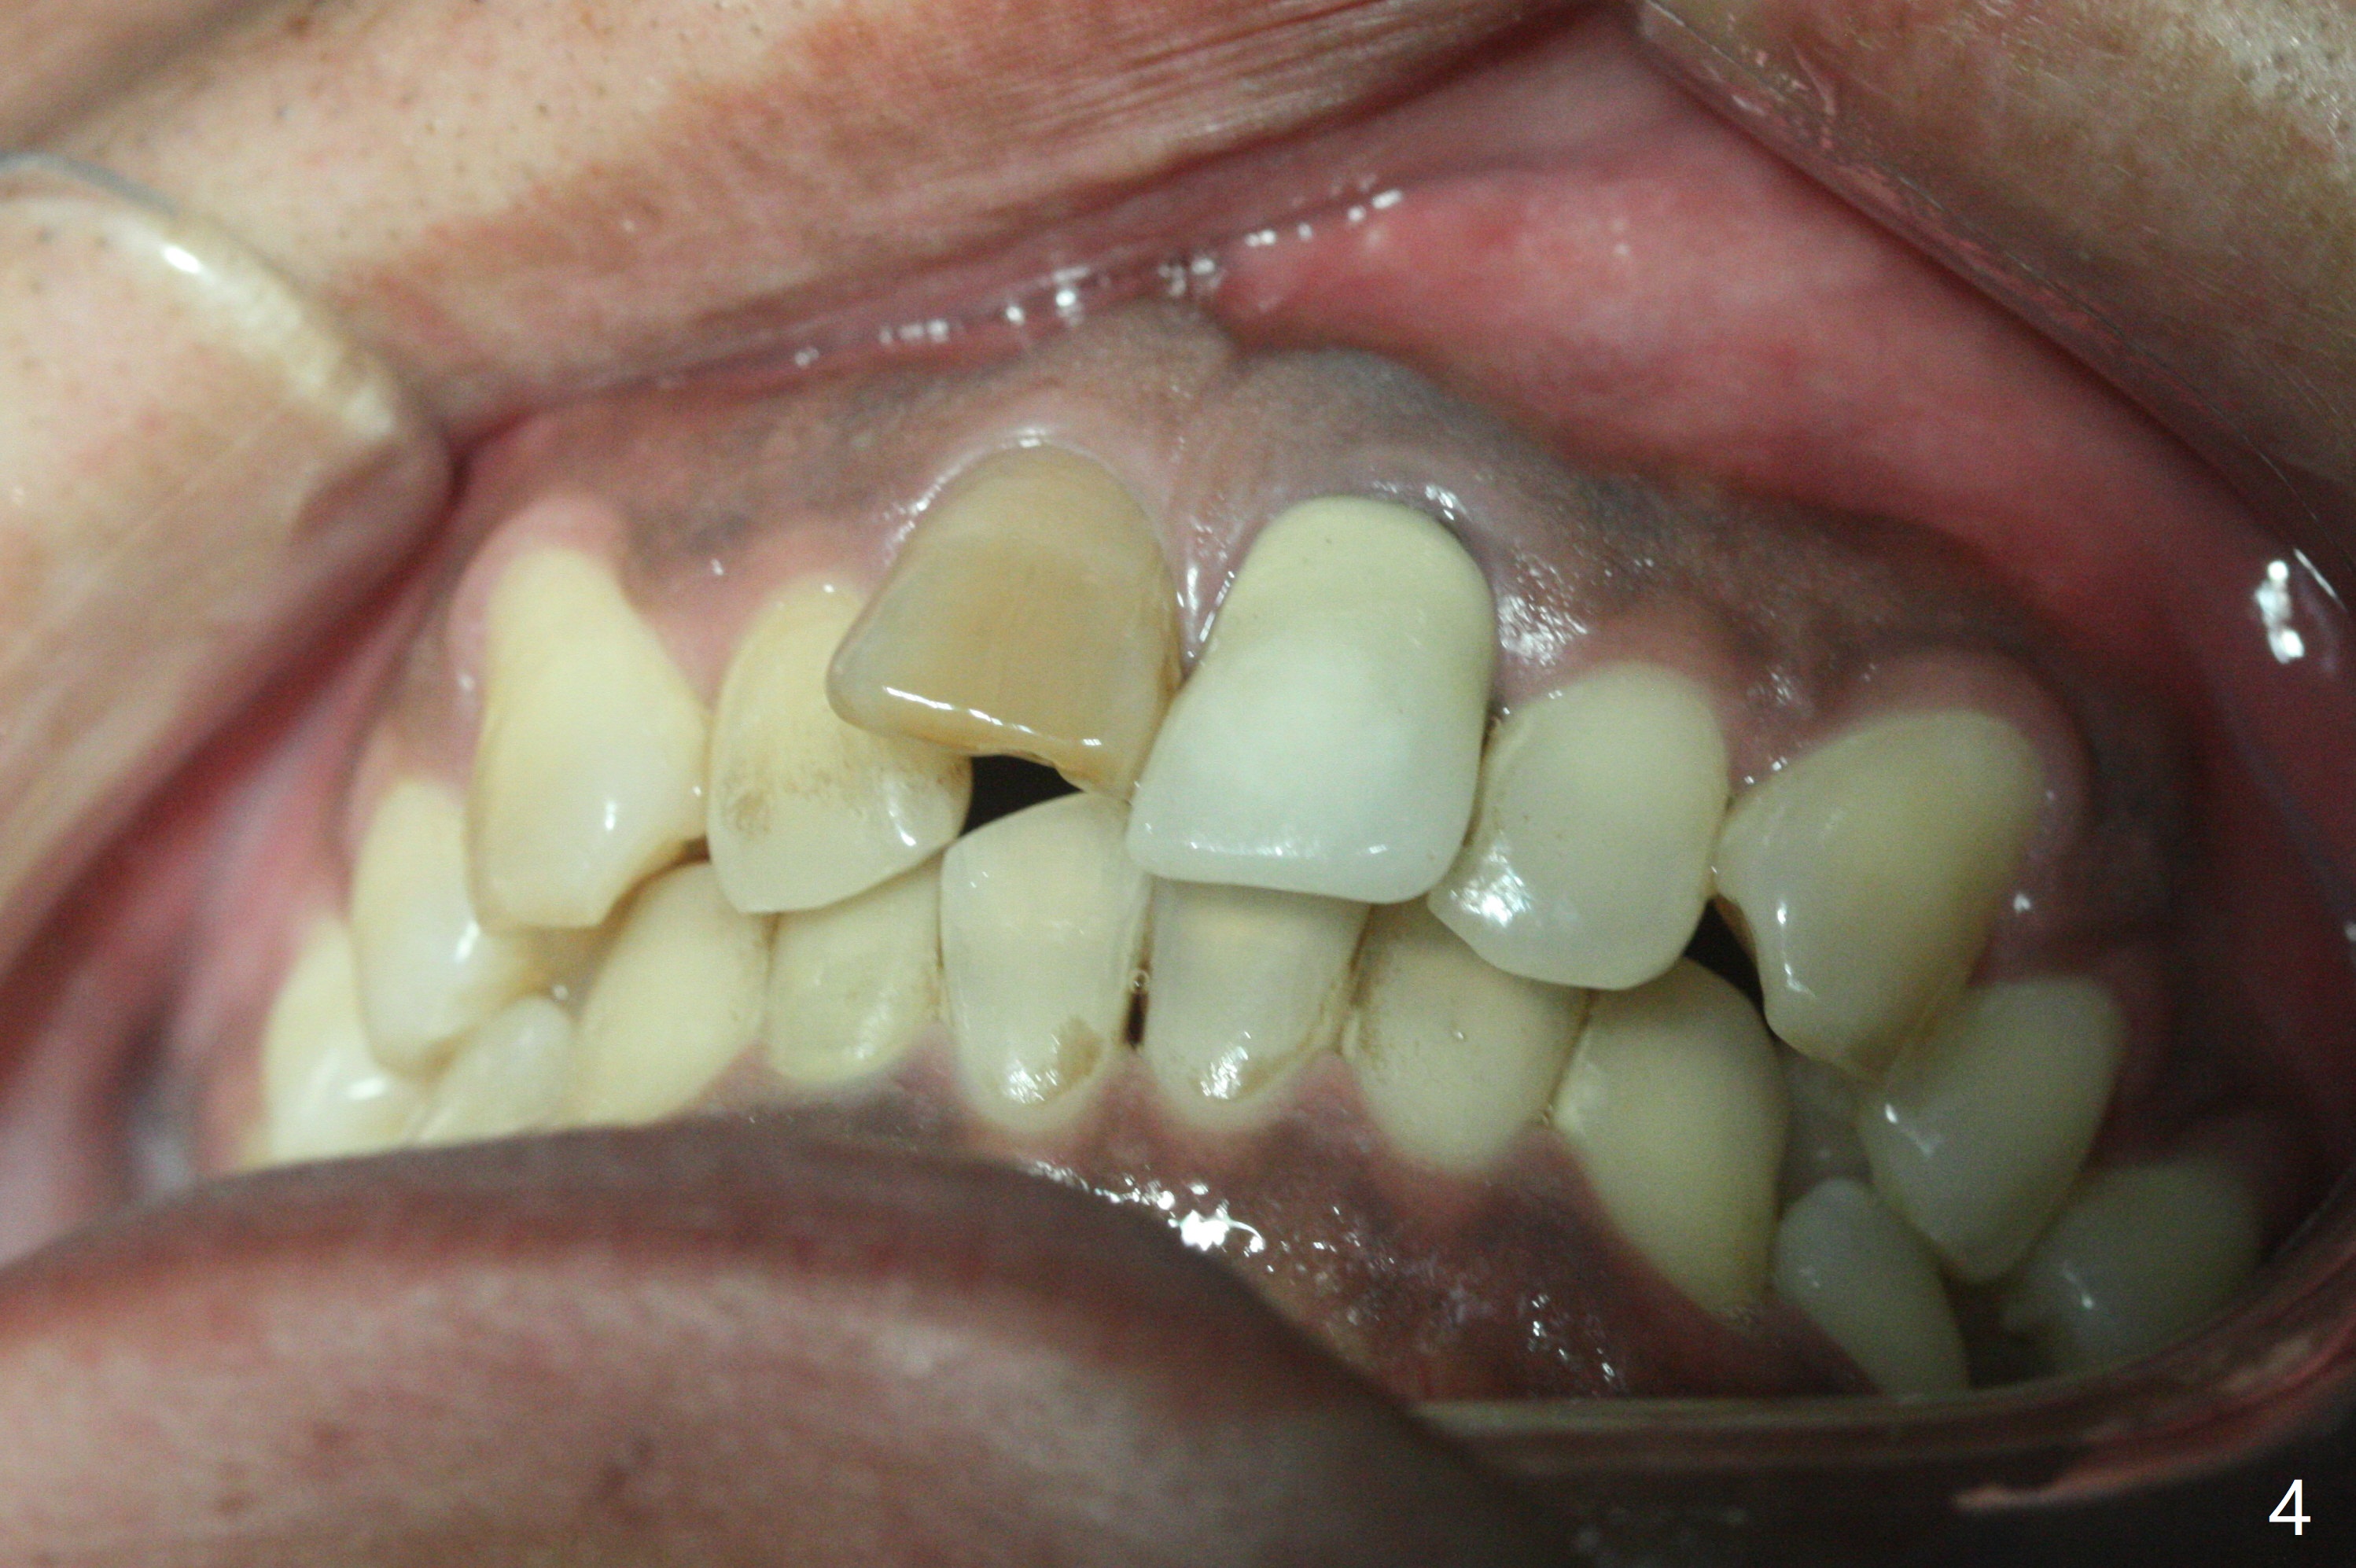

Class II半个牙。这个不用拔牙,Molar distalizaton 和expansion 就可以解决。Oral scan and submit it to Unismile. 建模后。我来帮您设计。张。两个中切牙,位置可以不用排得太完美。排到半程的位置,然后用重做的牙冠来调齐。这样,能减少一些复发的势能。Harry Hu